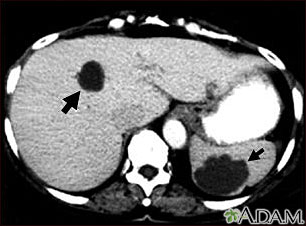

Esta TC abdominal muestra múltiples quistes en el hígado y el bazo. Se puede ver un quiste circular oscuro en el hígado (lado izquierdo de la pantalla) y un gran quiste circular irregular en el bazo (parte inferior derecha de la pantalla).